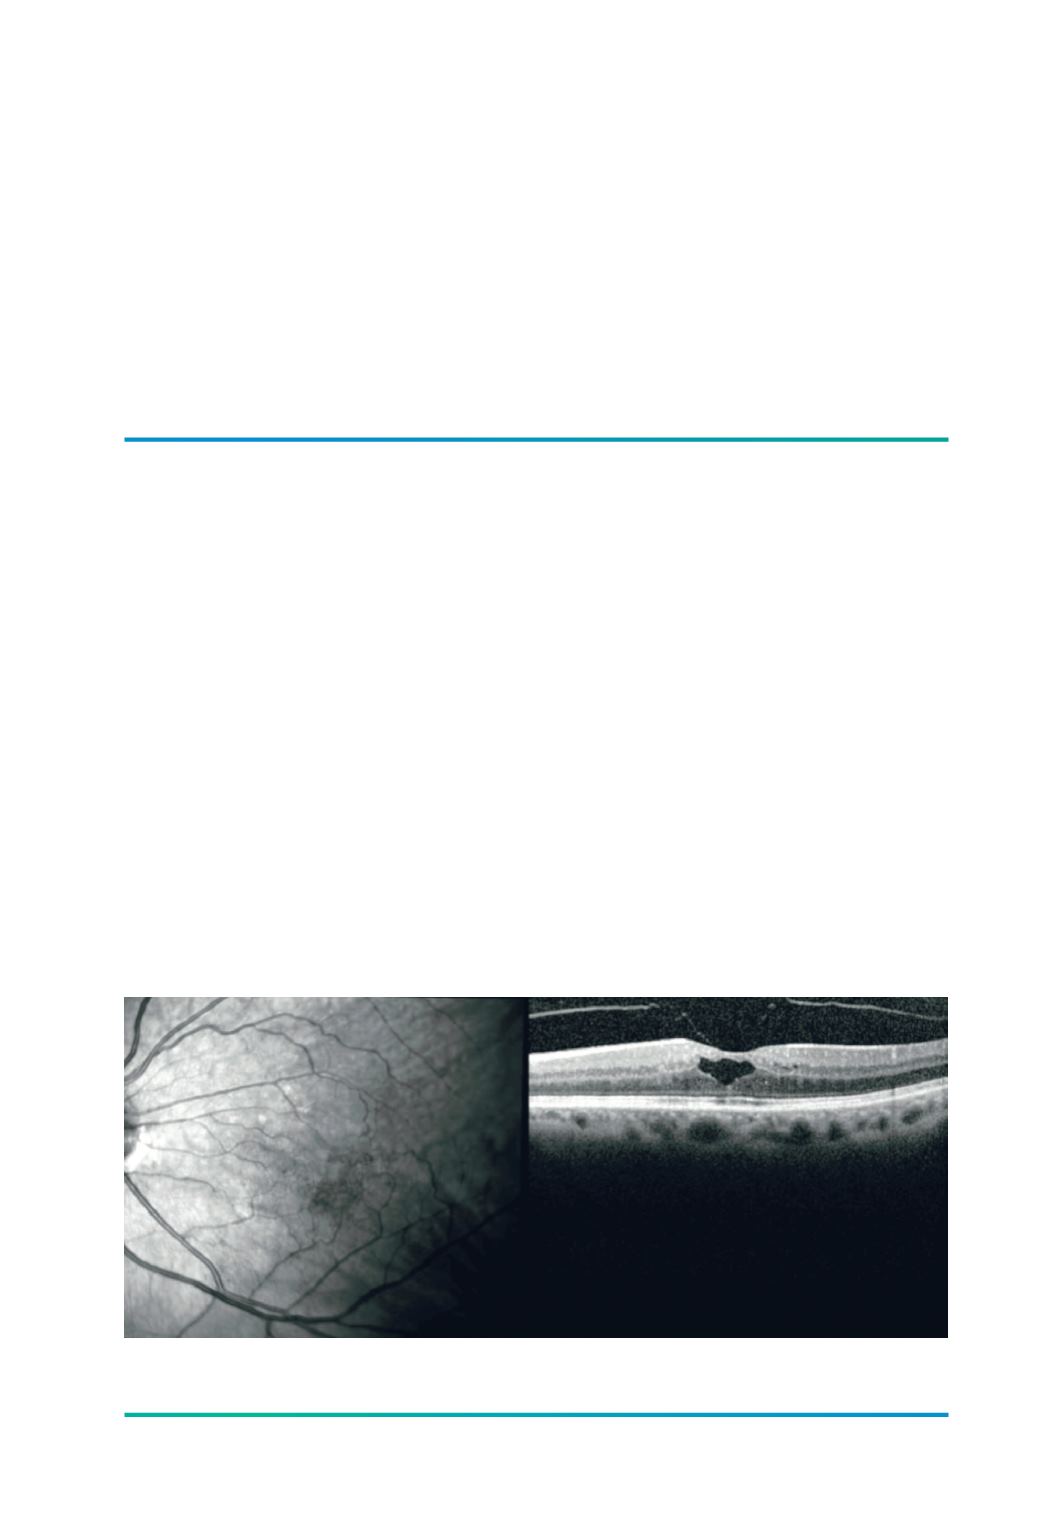

Figura 1.

Adesão vítreo-macular numa oclusão venosa com edema macular.